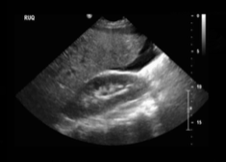

This positive finding on the FAST exam in the right upper quadrant indicates the presence of this.

What is free intraperitoneal fluid (hemoperitoneum)?